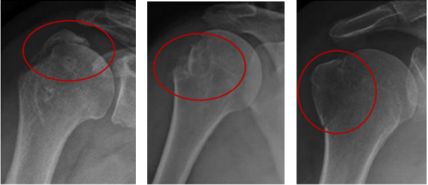

骨折分型:Neer分型

關(guān)鍵數(shù)據(jù):5毫米是決定手術(shù)與否的“黃金分割線”。研究表明,移位超過5毫米,保守治療后出現(xiàn)骨不連、畸形愈合和肩關(guān)節(jié)功能受限的風(fēng)險(xiǎn)顯著增加。